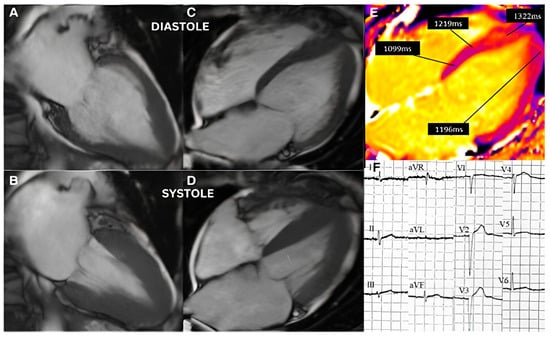

3.2. Imaging and Hemodynamic Observations

3.4. Integration of Acute and Chronic Stress Effects

4.1. Repeated Acute Stress, Takotsubo Cardiomyopathy, and Stressed Heart Morphology

4.5. Stressed Heart Morphology and Takotsubo Cardiomyopathy Pathophysiological Correlation